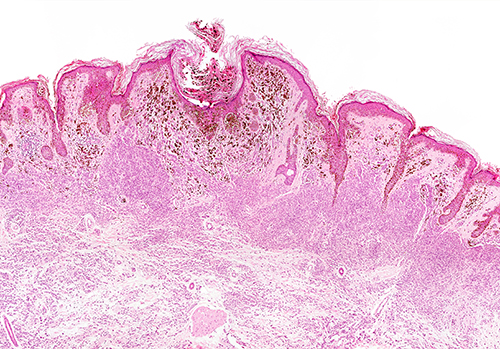

Founded in 1984, DCL Pathology is a College of American Pathologists (CAP) accredited laboratory and is internationally recognised as expert providers of clinical trial pathology services, with specific expertise in women’s health, urology, and oncology studies.

The Pathology facility operates in Carmel, Indianapolis, US, and is joining the collective network of Eurofins Clinical Trial Solutions facilities to enhance its service offerings, including providing histology, cytology, pathology, and molecular testing services such as DNA, RNA and Protein quantification, qPCR, and Next Generation Sequencing.

Their technical service expertise is uniquely positioned for serving pharma/biotech clients, as well as clinical CROs in the global clinical trial space and will complement the Eurofins Clinical Trial Solutions’ extensive portfolio of central laboratory, bioanalytical, biomarker, and molecular genomic testing services in support of clinical trials. This acquisition has resulted in Eurofins Clinical Trial Solutions being able to broaden its service offerings to clients, especially in the Oncology and Vaccine Development areas.